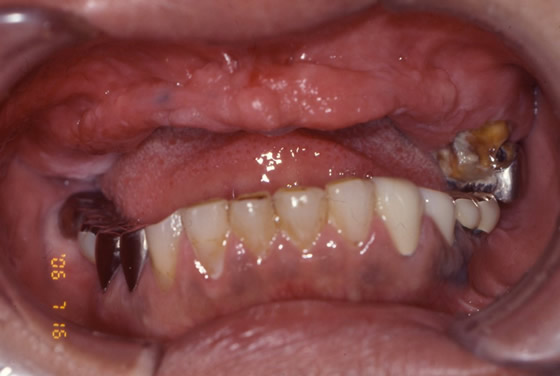

ボロボロの歯を包括治療で改善させたケース。